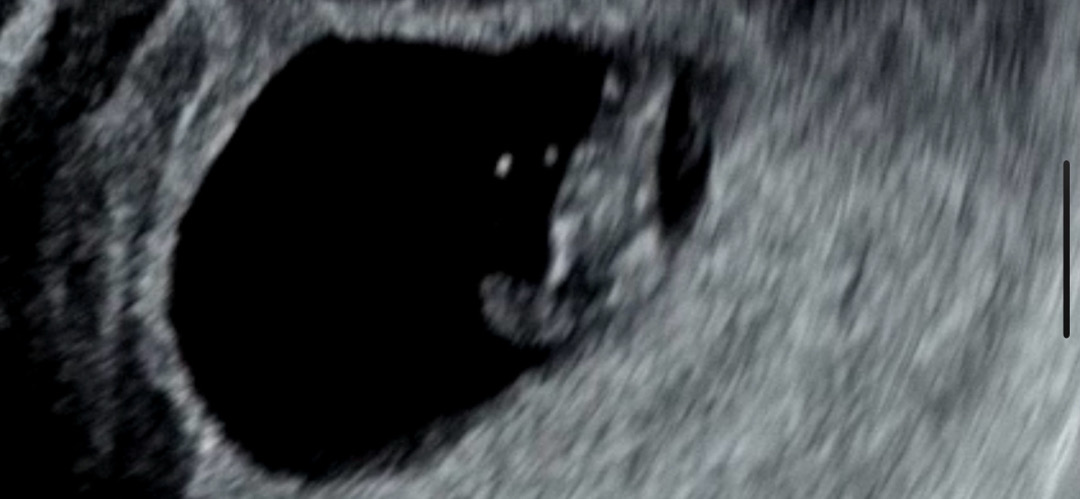

이거.. 다리 맞을까요..?

7주 땡 하자마자 심장소리 듣고 왔어요!! 지금 녹화된 영상 보고있는데.. 생닭같네요..? 다리 맞겠죠?!🤣🤣🤣 근데 가운데가 왜 도톰한거죠...?ㅋㅋㅋㅋㅋㅋㅋ큨ㅋㅋㅋ성별은 이미 정해져있는거라더니 설마..?

ㅋㅋㅋㅋㅋ안그래도 빌리에서는 2등신이랬는데🤣🤣 왜 생닭처럼 저리 보이는지용ㅋㅋㅋ 너무 웃겼어요 !! 얼른 9주에 하리보 보러 달려가고싶네요~~!!

7주에는 아직 팔다리가 없어용ㅋㅋㅋㅋ저 8주에도 안보였다가 9주에 보였어요!!

2등신이라규 알고있는데 저렇게 다리처럼 보이길래 뭔가 했어요🤣🤣🤣🤣